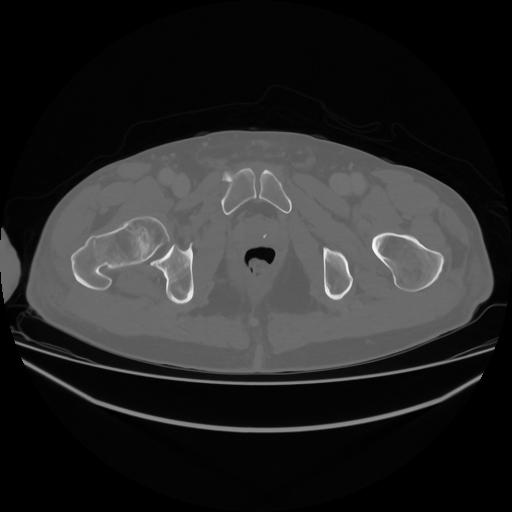

5 CUERPO,CE,Vol,1.0,CUERPO,,